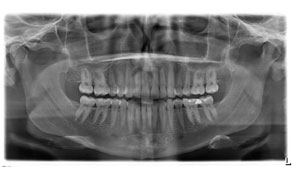

Bei länger unsauberen Verhältnissen entsteht eine sog. Parodontitis (im Volksmund Parodontose). Diese kann in verschiedensten Verlaufsformen in Erscheinung treten. In weiterer Folge wird der Zahnknochen abgebaut und dieser Zustand ist irreversibel. Über meist mehrere Jahre kann es so zur Zahnlockerung bzw. Zahnverlust kommen. Dabei kann diese chronische Erkrankung nur einzelne Zähne, einzelne Zahnareale aber auch das gesamte Gebiss befallen.

gesunder Zahnhalteapparat kranker Zahnhalteapparat